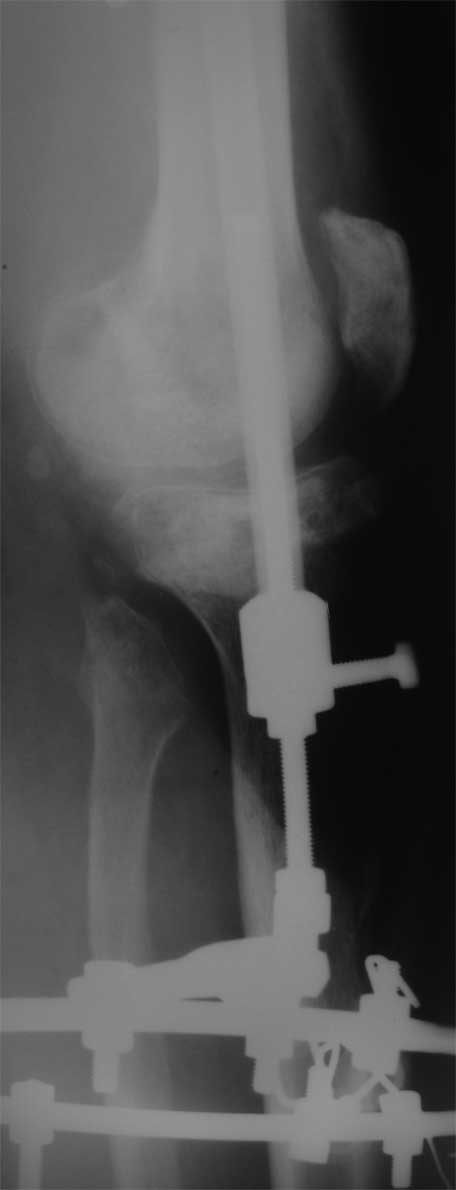

Костный и мягкотканый дефект голени

Поступил пациент 40 лет

Производственная травма. Лечился в гнойной хирургии - обширные раны голени. 7 мес пребывания в аппарате (на фото), по УЗИ - тромбоз глубоких вен с признаками реканализации.

Какую тактику лечения предпочесть? Планирую замещение костного дефекта цементом с а/б, укрыть латеральной головкой икроножной мышцы, на нее кожную пластику. Опыта подобных операций нет, переправить пациентка в другое, более сведущее ЛПУ не получается (ко всему прочему пациент абсолютно без денег, производство исчезло).

Предпочесть другие варианты, какие? Помогите с материалами по теме, книги, презентации, видео). Master technic b color atlas у меня есть).